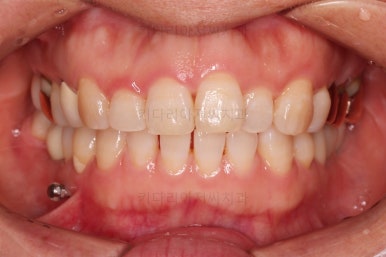

최종 사진을 보여드리겠습니다.

깔끔하게 마무리가 되었네요.

전후 비교입니다.

환자분도 치료에 만족하시어 미적으로 보기싫은 다른 금니들도 하나씩 교체하고 계신 중입니다.